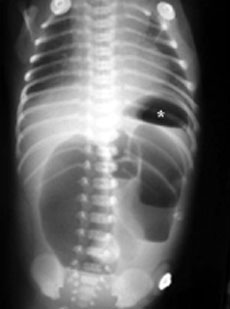

En neonatos, la obstrucción intestinal puede ser diagnosticada mediante una serie de hallazgos radiológicos característicos. La evaluación radiológica es crucial para diferenciar entre las diversas causas de obstrucción intestinal, que pueden ser de origen alto o bajo, y para determinar el manejo adecuado.

1. Radiografía Abdominal: Es la primera línea de imagen utilizada para evaluar la obstrucción intestinal en neonatos. Los hallazgos típicos incluyen dilatación de asas intestinales y la presencia o ausencia de niveles hidroaéreos, lo cual puede indicar si la obstrucción es proximal o distal. Por ejemplo, la «burbuja única» se asocia con atresia esofágica, la «doble burbuja» con atresia duodenal, y la «triple burbuja» con atresia yeyunal.[1-2]

2. Estudios de Contraste Gastrointestinal: Estos estudios son útiles para confirmar el diagnóstico y determinar la ubicación exacta de la obstrucción. Un enema de contraste puede mostrar un microcolon en casos de atresia ileal o colónica, y es particularmente útil para diagnosticar íleo meconial y enfermedad de Hirschsprung, donde se puede observar una zona de transición en el colon.[3-4]